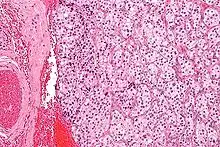

Micrograph of a carotid body tumor with the characteristic Zellballen. H&E stain.

On microscopic inspection, the tumor cells are readily recognized. Individual tumor cells are polygonal to oval and are arranged in distinctive cell balls, called Zellballen.[8] These cell balls are separated by fibrovascular stroma and surrounded by sustentacular cells.

By light microscopy, the differential diagnosis includes related neuroendocrine tumors, such as carcinoid tumor, neuroendocrine carcinoma, and medullary carcinoma of the thyroid.

With immunohistochemistry, the chief cells located in the cell balls are positive for chromogranin, synaptophysin, neuron specific enolase, serotonin, neurofilament and Neural cell adhesion molecule; they are S-100 protein negative. The sustentacular cells are S-100 positive and focally positive for glial fibrillary acidic protein. By histochemistry, the paraganglioma cells are argyrophilic, periodic acid Schiff negative, mucicarmine negative, and argentaffin negative.